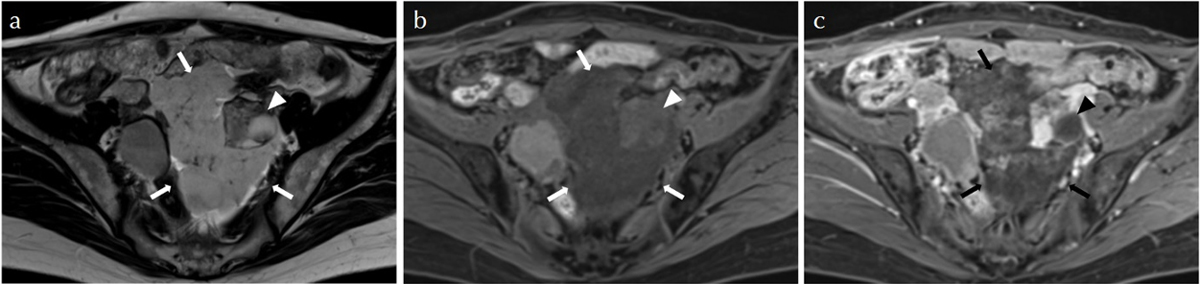

MRI:

両側卵巣に嚢胞構造(T2WI高信号、T1WI軽度低信号)

骨盤底部、右付属器表面に付着する腫瘤

明瞭なT2WI高信号、T1WI低信号、DWI高信号、ADC高値

右卵巣表面に連なるT2WI低信号の樹枝状構造

樹枝状構造は造影され、腫瘤本体は造影効果が弱い

少量の腹水と軽度腹膜肥厚